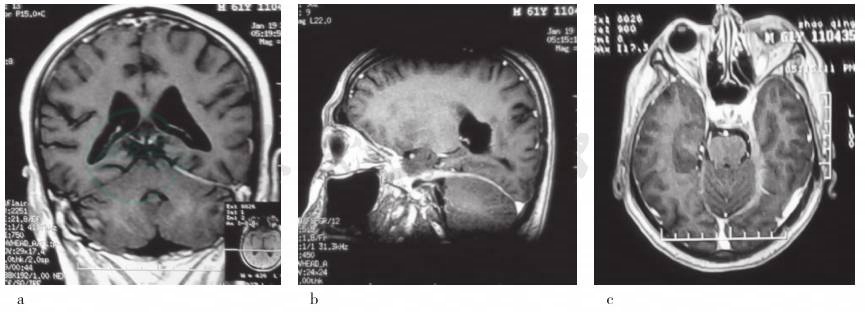

临床诊断为“抗中性粒细胞胞质抗体相关血管炎,继发性肥厚性硬脑膜炎”。为排除感染,明确病理性质后指导治疗,建议行硬脑膜组织活检术,患者及其家属顾虑相关风险拒绝。予泼尼松50mg/次、1次/d口服,每2周减量5mg,莫西沙星0.40g/次、1次/d口服抗感染,曲马多50mg/次、1次/晚口服镇痛,治疗10天后肝功能试验明显升高,考虑药物相关肝损伤可能,停用莫西沙星和曲马多,改为多烯磷脂酰胆碱(易善复)456mg/次、3次/d和甘草酸二铵(甘利欣)150mg/次、3次/d口服改善肝功能,体温恢复正常,症状明显好转。患者共住院28天,出院后1个月门诊随访,症状无反复,复查头部MRI增强显示增厚的硬脑膜变薄,强化征象减轻,病变范围缩小(图2)。

图2 治疗后复查头部MRI增强

a.冠状位增强T1WI显示左侧小脑幕病变范围缩小;b.矢状位增强T1WI显示增厚的硬脑膜变薄,病变范围缩小;c.横断面增强T1WI显示左侧海绵窦、颞区硬脑膜变薄,病变范围缩小